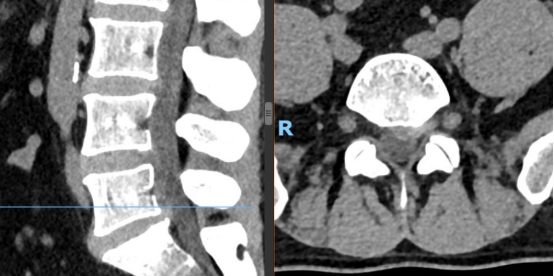

如果说UBE技术是脊柱治疗的“精准镜手”,那么3D打印技术就是定制化治疗的“私人裁缝”。针对每一位脊柱疾病患者的个体差异,医生通过高精度CT扫描,获取患者脊柱的三维立体数据,利用3D打印技术1:1还原脊柱的解剖结构——从椎体形态、椎间盘位置,到神经走行、病变范围,都能精准复刻,形成专属的脊柱模型。基于此模型,医生术前可以进行精准规划:模拟手术路径、预判操作风险、选择适配的内固定器械,甚至打印定制化的椎间融合器、内固定支架,确保手术操作“有的放矢”,贴合患者的个体解剖特征,避免传统手术中“凭经验操作”的不确定性,让脊柱治疗从“标准化”走向“个性化”,极大提升了手术的精准度与安全性。

1.术前规划更精准:通过3D打印脊柱模型,医生可直观掌握患者的病变细节,提前设计最佳手术路径,避开神经、血管等重要组织,降低手术风险;